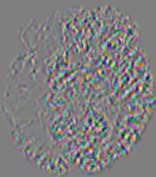

4.3.1 Advection Imaging via Advection-Diffusion

Slice #1Slice #2Slice #3Slice #4Slice #5Slice #6𝐕gt𝟐subscriptnormsuperscript𝐕gt2\|\bf{V}^{\text{gt}}\|_{2}Refer to captionRefer to captionRefer to captionRefer to captionRefer to captionRefer to caption𝐕est𝟐subscriptnormsuperscript𝐕est2\|\bf{V}^{\text{est}}\|_{2}Refer to captionRefer to captionRefer to captionRefer to captionRefer to captionRefer to captionRefer to caption1.51.51.51.21.21.20.90.90.90.60.60.60.30.30.30.00.00.0(mm/s)𝑚𝑚𝑠(mm/s)Destsuperscript𝐷estD^{\text{est}}Refer to captionRefer to captionRefer to captionRefer to captionRefer to captionRefer to captionRefer to caption0.0150.0150.0150.0120.0120.0120.0090.0090.0090.0060.0060.0060.0030.0030.0030.0000.0000.000(mm2/s)𝑚superscript𝑚2𝑠(mm^{2}/s)

Figure 14: PIANO identifiability testing: advection imaging via advection-diffusion. Top row shows 𝐕gt2subscriptnormsuperscript𝐕gt2\|{\bf{V}}^{\text{gt}}\|_{2} used for simulating ground truth pure advection. Rows below show the estimated 𝐕est2subscriptnormsuperscript𝐕est2\|{\bf{V}}^{\text{est}}\|_{2} and Destsuperscript𝐷estD^{\text{est}} on corresponding slices. Note that the plotted value scale for Destsuperscript𝐷estD^{\text{est}} is 0.01 of that for 𝐕gt2subscriptnormsuperscript𝐕gt2\|{\bf{V}}^{\text{gt}}\|_{2} and 𝐕est2subscriptnormsuperscript𝐕est2\|{\bf{V}}^{\text{est}}\|_{2}.

We use the same ‘Advection Imaging’ simulation of Sec. 4.2.1 as the concentration dataset for PIANO. However, instead of modeling pure advection (Eq. 15), we let PIANO estimate both velocity 𝐕estsuperscript𝐕est{\bf{V}}^{\text{est}} and diffusivity Destsuperscript𝐷estD^{\text{est}} via the advection-diffusion PDE (Eq. 2) underlying the proposed PIANO model. Fig. 14 shows the estimated 𝐕est2,subscriptnormsuperscript𝐕est2\|{\bf{V}}^{\text{est}}\|_{2}, and Destsuperscript𝐷estD^{\text{est}} fields for one patient. Although PIANO has the freedom to estimate both a velocity and a diffusivity field from pure advection, PIANO differentiates well between advection and diffusion: the estimated 𝐕est2subscriptnormsuperscript𝐕est2\|{\bf{V}}^{\text{est}}\|_{2} successfully reproduces the ground truth 𝐕gt2subscriptnormsuperscript𝐕gt2\|{\bf{V}}^{\text{gt}}\|_{2} governing the simulated advection process, just as it already did in the ‘Advection Imaging via Advection’ test (Fig. 12). More importantly, the estimated diffusivity Destsuperscript𝐷estD^{\text{est}} is orders of magnitudes smaller than 𝐕est2subscriptnormsuperscript𝐕est2\|{\bf{V}}^{\text{est}}\|_{2}, indicating the estimated diffusion is negligible compared to the estimated advection, which is highly consistent with the underlying pure advection of the simulated data.